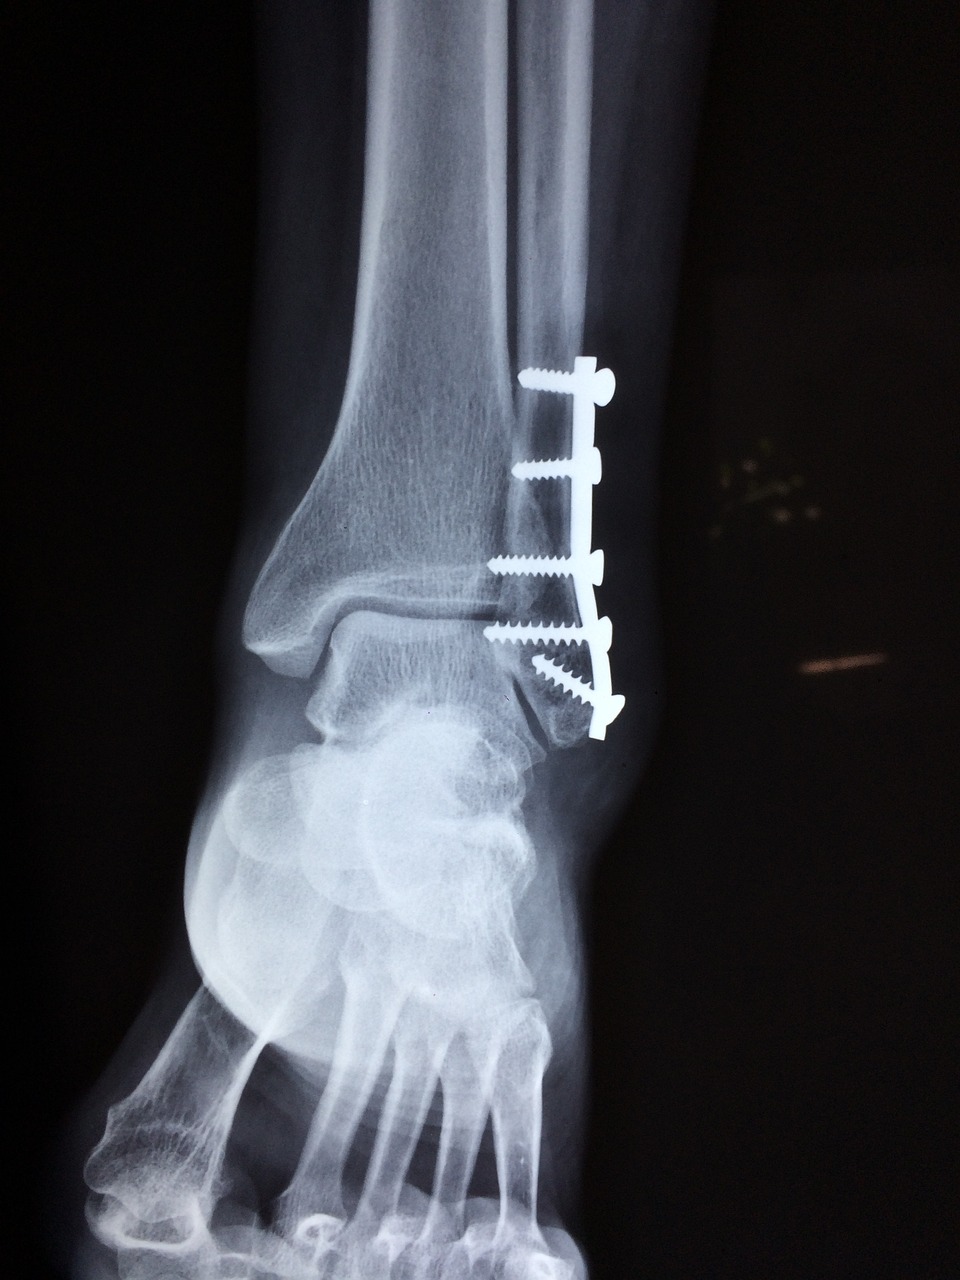

뼈 건강을 유지하기 위해서는 정기적인 건강 검진이 필요합니다. 특히, 나이가 들어감에 따라 골밀도 검사를 통해 뼈의 상태를 체크하는 것이 중요합니다. 골다공증이나 골밀도 감소는 뼈가 약해져 쉽게 부러지게 만들 수 있으므로, 조기에 발견하고 예방하는 것이 필요합니다.